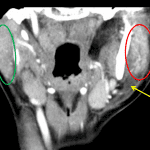

- Enlarged, hyperenhancing left parotid gland with adjacent fat stranding extending into the left masticator and left parapharyngeal spaces

- No loculated fluid collection

- Reactive cervical lymphadenopathy without suppurative nodal disease or venous thrombosis

- Acute left parotiditis

Acute left parotiditis with surrounding fat stranding but no evidence of abscess or airway compromise.

Reactive cervical lymphadenopathy without suppuration or venous thrombosis.